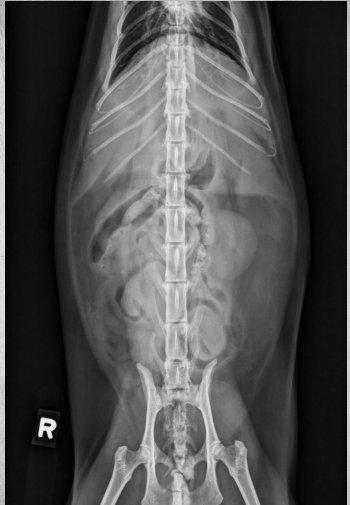

15 yo cat

Weight loss, anorexia, vomiting

Findings:

● Dilated bowel filled with fecal mass

– Not only large intestine, but small

intestine as well.

● Megacolon